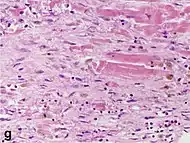

Histopathological examination of the heart may reveal infarction at autopsy. Under the microscope, myocardial infarction presents as a circumscribed area of ischemic, coagulative necrosis (cell death). On gross examination, the infarct is not identifiable within the first 12 hours.[20]

Although earlier changes can be discerned using electron microscopy, one of the earliest changes under a normal microscope are so-called wavy fibers.[21] Subsequently, the myocyte cytoplasm becomes more eosinophilic (pink) and the cells lose their transversal striations, with typical changes and eventually loss of the cell nucleus.[22] The interstitium at the margin of the infarcted area is initially infiltrated with neutrophils, then with lymphocytes and macrophages, who phagocytose ("eat") the myocyte debris. The necrotic area is surrounded and progressively invaded by granulation tissue, which will replace the infarct with a fibrous (collagenous) scar (which are typical steps in wound healing). The interstitial space (the space between cells outside of blood vessels) may be infiltrated with red blood cells.[20]

These features can be recognized in cases where the perfusion was not restored; reperfused infarcts can have other hallmarks, such as contraction band necrosis.[23]

| Macrophages and lymphocytes | 3–5 days | 5–10 days (including ‘siderophages’) | 10 days to 2 months | ![]() |